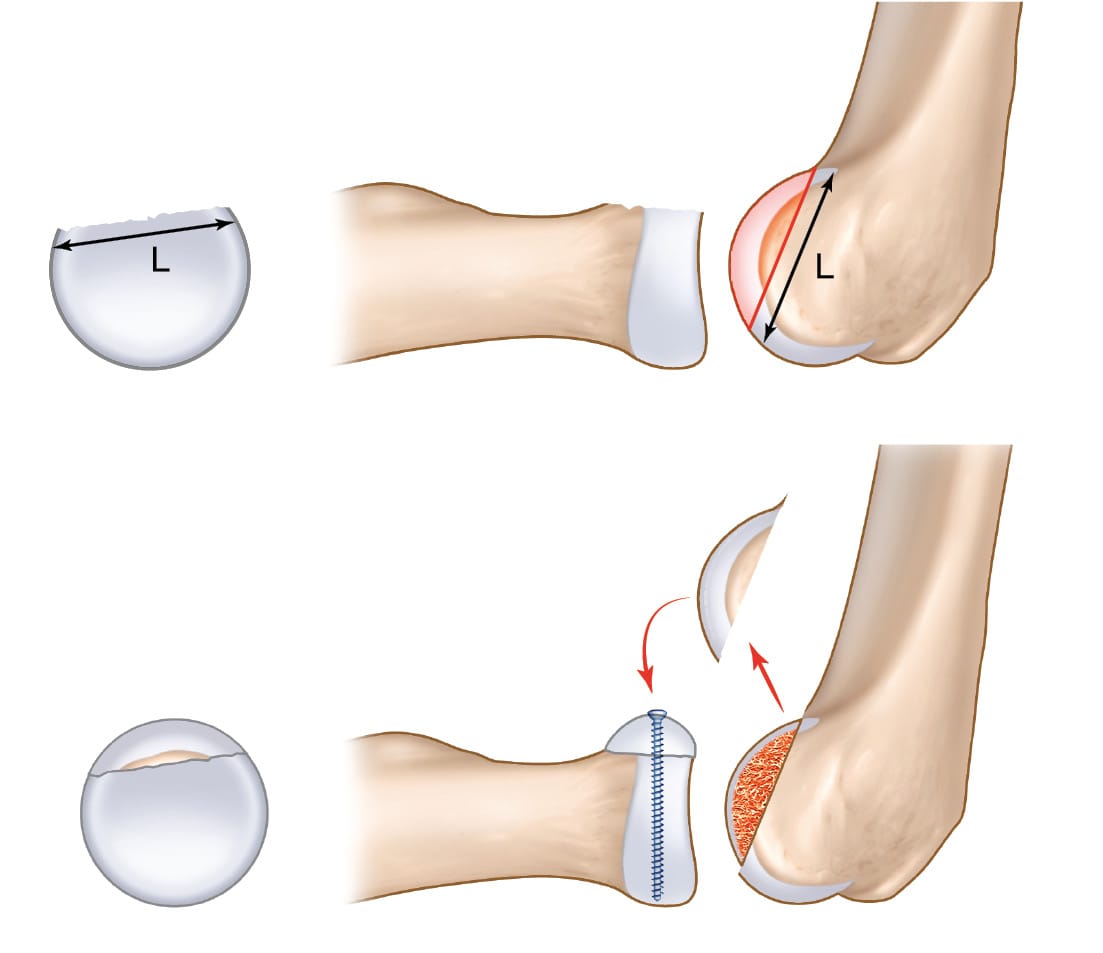

A lateral approach is used to open the radiohumeral compartment; this may be easier if there is an injury to the lateral collateral ligament, which is often part of the picture in complex joint trauma. Exposure of the radial head, the bone fragments and capitellum follows the same method whether for ORIF or replacement. Related interventions, such as coronoid process ORIF or reinsertion of the anterior capsule, are performed. A standard ORIF is carried out by reducing the fragments and temporary fixation with pins. This is followed by an assessment of bone loss: circular segment or chunk. The bone loss contour is mapped onto the lateral surface of capitellum. If the segment is circular (Figure 1), the length of the line is measured and transferred. A mini oscillating saw is using to harvest a graft with a sagittal thickness of 4–5 millimetres, depending on the extent of bone loss. The ORIF is performed using mini screws of 1.5 or 2mm diameter (Figure 2), with or without a console plate, exercising caution in the “safe zone” to avoid any proximal radio-ulnar impingement. A cancellous bone graft can also be harvested if necessary. The osteochondral graft is harvested in the sagittal plane and positioned in the axial plane, with the lateral surface of capitellum (the graft) becoming the superior surface of the radial head.